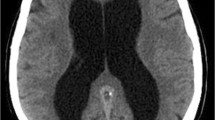

Hydrocephalus is a condition which is characterized by head enlargement in infants due to enlargement of brain ventricles. An excess of fluid secretion and collection of fluid within the brain cavities are treated as Hydrocephalus. The extra fluid puts stress on the brain and can damage the brain. Hence, the increase in the fluid level in the brain's cavities may increase intracranial pressure and lead to brain damage. It is most usual in infants on children and rarely in the adult age group. Children often have a full life span if hydrocephalus is early detected and treated. This paper presents various data mining techniques and used to find out the disease in an early manner. Magnetic resonance imaging is one of the detection tools which is used to predict the disease properly. This approach includes the basic four data mining processes, namely preprocessing, segmentation, feature extraction, and classification as stage-by-stage manner using MRI dataset. Along with this process, the tree augmented Naïve Bayes nearest neighbor (TANNN) algorithm is also implemented to improve the accuracy in detecting the disease and also gave the best detection rate. The TANNN algorithm may provide the best results in diplomatic, uniqueness, perfection, and overall running time. The first stage in the data mining technique is preprocessing, which converts the original data into a useful format. The second stage is a key technique, and it groups the original data into possible divisions according to its category. The third stage is feature extraction, which is used to extract the needed data from the source. The fourth stage is the classification that appoints data in a collection to destination categories or data groups. This paper also concentrates on image mining, which includes experiments in image elements such as texture, shape, and size. Image classification is an important task in the field of medicine and technology. This helps the radiologist in the process of diagnosing hydrocephalus.